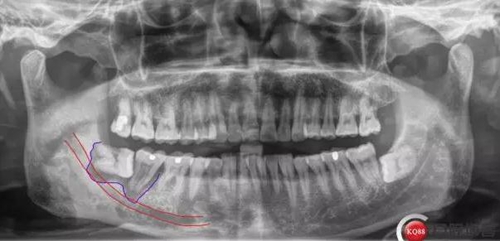

X線及CBCT檢查:47、48根尖周區(qū)大面積低密度影像,波及下牙槽神經(jīng)管,部分區(qū)域至神經(jīng)管以下。CBCT顯示神經(jīng)管走形于47根尖炎癥區(qū)下方(已侵犯)48炎癥區(qū)頰側(cè)(已侵犯)

術(shù)前CBCT分析

對(duì)于曲面斷層片的分析,當(dāng)智齒埋伏牙的根尖與下牙槽神經(jīng)有重疊影像時(shí),常??刹捎糜^察重疊部分牙根的牙周膜和硬骨板是否連續(xù),下頜管是否比牙根密度高,下頜管是否變窄等,來辨別牙根與神經(jīng)管的位置關(guān)系。當(dāng)然曲面斷層片也很難避免其失真變形的自身局限性。拍攝CBCT能更為直觀預(yù)估其風(fēng)險(xiǎn)。但切記盲目的嘗試和挑戰(zhàn)。